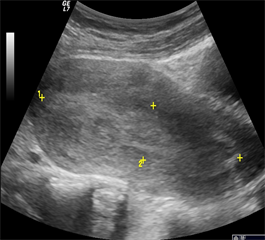

27 (22.3%) women were diagnosed with incomplete abortions. This rate is comparable to that of Yang and al, who found a rate of 23.1% [9] . Persistent vaginal bleeding after an abortion may be due to retained trophoblastic tissue, but these women may also present with symptoms of infection, including pain and fever [10] . Findings on US are heterogeneous hypoechoic material in the endometrial cavity consistent of retained trophoblastic tissue and blood clots (Figure 2).

Figure 2. Retained products of conception in the uterine cavity.